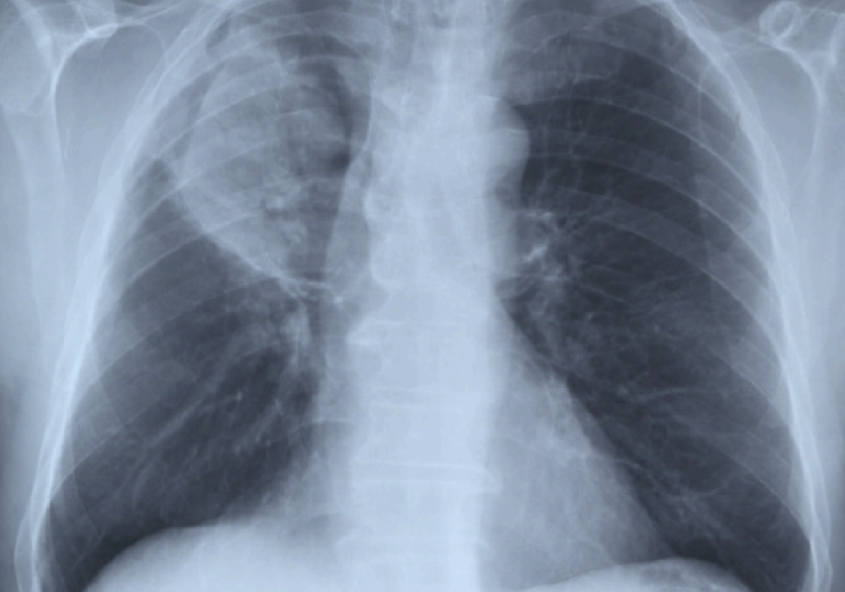

Catamenial Pneumothorax: A Challenging Diagnosis

Catamenial pneumothorax is the most frequent manifestation of thoracic endometriosis: this article is about a case in which the diagnosis was formulater only when a temporal connection with menstrual bleeding was noticed and when implementation of a specific medical treatment was able to prevent further recurrences of the desease.